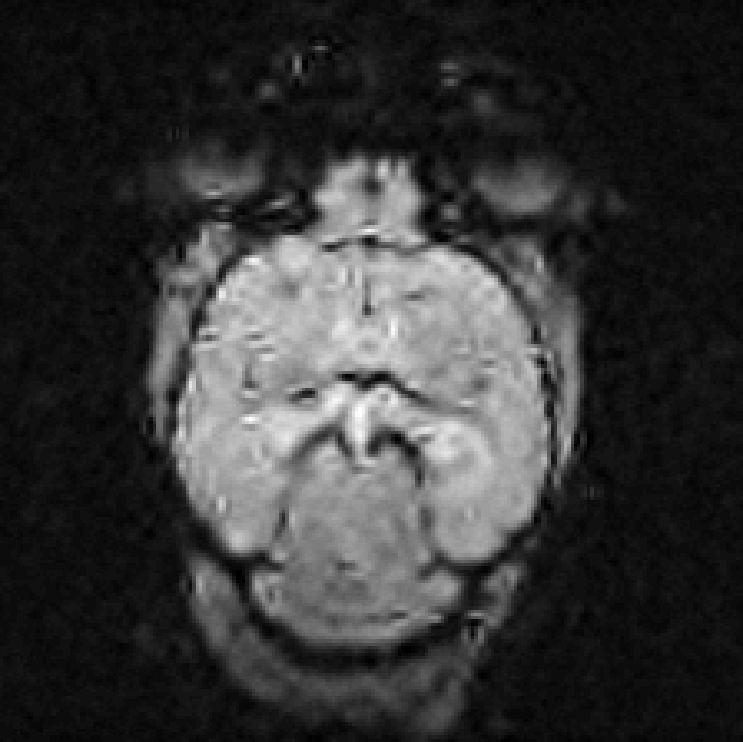

3.2.2 3D angiography

Using the same method as in 2D, namely TSP-sampling and projection onto the set of constraints, we reconstructed volumes from 3D -space. In order to estimate the quality of the reconstructions, we compared the angiograms computed from the 3D images using Frangi filtering [19]. The results are shown in Fig. 3 for acceleration factors (Fig. 3(b,e)) and (Fig. 3(c,f)) and compared to the angiogram computed from the whole data.

Using the strategy described in Part 3.1 the time to traverse -space would be 3.53 s (full acquisition), 3.15 s () and 0.88 s (). The main drawback of TSP-based sampling schemes is that the time reduction is not directly proportional to , in contrast to classical 2D downsampling and reading out along the third dimension. Nevertheless, if the number of measurements is fixed, the TSP-based approach leads to more accurate reconstruction results since the sampling scheme may fit any density [7].

Angiograms shown in Fig. 3 illustrate that one can reduce the travel time in the -space and still observe accurate microvascular structure. If , time reduction is minor (about 10% less), but the computed angiogram is almost the same as the one obtained with a complete -space. It is interesting to notice that with a higher acceleration factor (), the acquisition time is reduced by 75%, but the computed angiogram remains of good quality. The angiogram appears a bit noisier, especially in the pre-injection setting (Fig. 3(c)), but the post-injection image allows recovering Willis polygon and most of the major vessels of the mouse brain (Fig. 3(f)).